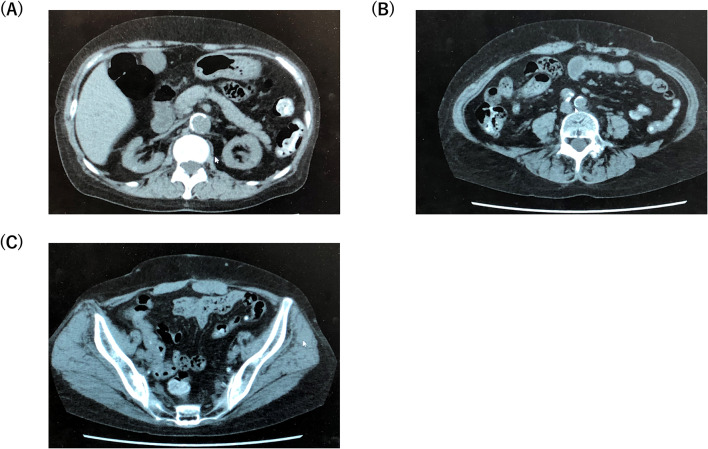

Fig. 2.

Computed tomography scanned just after the removal of the PD catheter. Computed tomography captured at the levels of (a) kidney, (b) aortic bifurcation, and (c) pelvis. PD peritoneal dialysis

On admission, the patient was alert. Her blood pressure was 194/108 mmHg, heart rate was 88 beats/min, and body temperature was 35.8 °C. Physical examination revealed she was experiencing a moderate degree of abdominal pain and tenderness. Her exit site and catheter tunnel showed no evidence of infection. Laboratory data on admission revealed a white blood cell count of 11,220/μL with 83.3% segmented neutrophils and C-reactive protein level of 0.09 mg/dL. Serum procalcitonin was negative. A summary of laboratory data on admission is shown in Table 1. The dialysate fluid cell count was 4194 white blood cells/μL. Gram stain of the cloudy peritoneal dialysate revealed Gram-negative bacilli (Fig. 1), whereas Ziehl–Neelsen stain of the dialysis fluid was negative. To identify the causative bacteria, we collected PD fluid from the PD bag (that dwelled in the abdominal cavity of the patient) in 10-mL or 50-mL sterilized tubes. Next, cloudy PD solution in the tubes was centrifuged, resuspended with saline, and plated on standard sheep blood agar plates. Additionally, 10 mL of cloudy PD solution was incubated in a blood culture bottle. Once bacterial colonies were formed, they were then submitted for conventional biochemical analyses to determine the bacteriological features of the bacterium and to group it into a known bacterial genus. Blood culture was also negative. A tentative diagnosis of bacterial peritonitis was established, and the patient was treated empirically with intraperitoneal administration of 1 g/day ceftazidime and 1 g/day vancomycin. Three days after starting treatment with the two antibiotics, cell count in the peritoneal dialysate decreased and fever and abdominal pain subsided. Although the causative bacterium formed colonies on the agar plate, standard biochemical analysis failed to identify the genus, and the sample was then subjected to matrix assisted laser desorption/ionization-time of flight (MLADI-TOF) mass spectrometry. However, mass spectrometry also failed to identify the genus, and the sample was sent for 16S ribosomal RNA gene sequencing analysis. On the 7th hospital day, results of the susceptibility test were returned and showed the causative bacterium was susceptible to ciprofloxacin, levofloxacin, meropenem, and doripenem, and resistant to penicillin, piperacillin, cefoperazone, trimethoprim/sulfamethoxazole, and vancomycin. Therefore, we continued intraperitoneal administration of ceftazidime (Table 2). However, on the 10th hospital day, her serum C-reactive protein level was re-elevated, cell count in the peritoneal dialysate increased to 5498 cells/μL, and gram-negative bacilli were again detected, suggesting flare-up of bacterial peritonitis by the same organism, namely, relapsing peritonitis. To rule out the possibility of intestinal perforation, contrast-enhanced computed tomography was performed, but no evidence of perforation was found. At this point, ceftazidime was ineffective against the Gram-negative bacilli. Therefore, we replaced ceftazidime with meropenem and subsequently discontinued vancomycin. On the 16th hospital day, the results of 16S ribosomal RNA gene sequencing analysis were returned and revealed that the causative organism was Stappia indica sp. Intraperitoneal administration of meropenem was continued for a total of 21 days, resulting in a normalized cell count in the peritoneal dialysate and negative culture at the end of the therapy. Given the three distinct prior episodes of bacterial peritonitis, we discontinued PD and initiated hemodialysis to lower the risk of developing encapsulating peritoneal sclerosis, and established an arteriovenous fistula on her right forearm on the 30th hospital day. However, on the 37th hospital day (7 days after discontinuing meropenem), peritonitis recurred. The bacteria detected from the cloudy dialysate were Gram-negative bacilli and later reconfirmed as Stappia indica. Because repeated relapse of bacterial peritonitis under sensitive antibiotics treatment was observed, biofilm formation was highly suspected. Accordingly, the peritoneal catheter was surgically removed on the 43rd hospital day. Macroscopically, the removed catheter did not show apparent biofilm formation. Then, computed tomography was performed, and no infection source including intra-abdominal abscess was detected (Fig. 2). To further determine whether biofilm formation was present, the tip of the removed PD catheter was cut at the tip and cultured by being submerged in the liquid medium in order that the bacteria in the biofilm located in both inner and outer surfaces of the PD catheter could easily access the medium and yield a positive culture.